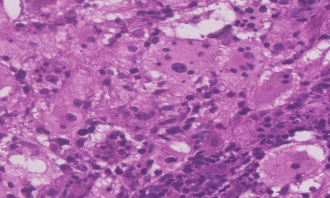

31 year old female presented to us with complaints of limp while walking from past few months. No history of fever, loss of appetite, weight loss or any other constitutional symptoms. Patient is a post operated case of Medulloblastoma brain and occipital craniotomy with VP shunting was done in May 2018 in London for the same along with adjuvant chemo-radiation. Patient received craniospinal radiotherapy (35Gy/21fractions) + (20Gy/12 fractions) for approx. 6 weeks in Aug-Sep 2018. Patient received 6 cycles of Cisplatin, Vincristine and Lomustine, during Sep 2018-Dec 2018. Patient was on regular follow up and regular MRI Brain was done during follow up and patient was asymptomatic during the time period of last 4 years, until last month when she developed sudden onset right lower limb limp while walking. Patient was evaluated for above mentioned complaints and relevant scans were done. On X ray (Fig. 1),   MRI (Fig. 2) and PET scan (Fig. 3) multiple lytic lesion were seen involving D7 vertebra, right ischium and left proximal femur. Left proximal femur lesion was measuring 5.5 x 3.8 x 3.2 cm with a cortical breach. CT guided biopsy from D7 vertebra was done which showed typical emperipolesis (Fig. 4) S/O Rosai Dorfman Disease. IHC was done and was positive for S100 and CD68 suggestive and negative for CD1a suggestive of Rosai Dorfman Disease. High risk of pathological fracture of left proximal femur (Mirel’s Score – 11) was explained to the patient and cemented bipolar hemiarthroplasty was done for left hip. Post op patient was mobilized on Day 1 and dressing was changed at Day 5 and patient was discharged at Day 6. Final histopathology impression was s/o Extranodal Rosai Dorfman disease.

Fig. 4 Histopathological images showing emperipolesis in RDD